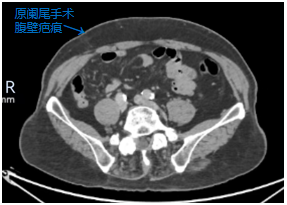

今年65岁的王先生来自邻近省份,被确诊为升结肠癌,同时合并有冠心病、糖尿病史,既往有腰椎内固定术、因房颤行心脏射频消融术病史,更棘手的是,他在多年前因胃溃疡穿孔、阑尾炎接受过传统的开腹胃部分切除术、阑尾切除术。此次患病,当地医院评估认为,其腹腔内因既往两次的胃肠道手术可能存在广泛粘连,解剖结构改变,再次行腹腔镜手术难度极大,易导致副损伤,建议行开放手术。然而,开放手术创伤大、恢复慢,王先生及其家属渴望能寻求一种更微创、更快速的康复方案。经多方打听和朋友推荐,他们了解到我院胃肠外科二病区在处理复杂腹腔肿瘤及腹腔镜微创手术方面经验丰富,毅然决定跨越省界,前来就医。

面对患者的这份沉甸甸的信任,我院胃肠外科二病区高度重视。科主任组织结直肠癌MDT团队及全科医护人员进行了深入的术前讨论。专家们一致认为,患者合并有较多内科疾病病史,围手术期治疗各科紧密协作,可确保基础疾病平稳控制;既往的开腹手术史,必然导致腹腔内脏器与腹壁、肠管之间形成的粘连,这如同在腹腔内设置了一个“迷宫”,使得再次手术的视野暴露、组织分离变得异常困难,术中损伤肠道、血管等重要组织的风险显著增加。